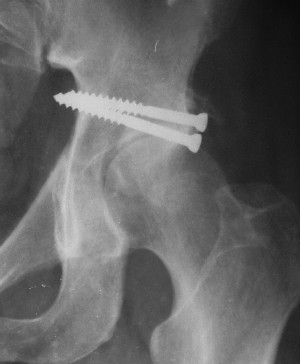

Привет! Вот недавно прооперировали похожий на ваш случай - впадина + шейка (правда у нас впадина поперечный+задний край). После травмы прошло 4 недели. мужчине 46 лет. С такой комбинацией все показания к первичному протезированию. Морально и технически мы к этому уже созрели.Но больной не собрал денег на протез. Выполнили остеосинтез впадины и шейки, прекрасно понимая, что головка вскоре рассосется, мы хотя бы надемся что к этому времени таз срастется, как говорится создали все условия для дальнейшего протезирования (может, и протез в последующем подешевле будет, в смысле, без укрепляющего кольца?). Привет Рункову!

Привет Алекей! Сделано неплохо, поздравляю, хотя второй винтик можно было бы и подлиннее в шейку загнать! Пара вопроов: доступ такой же? головка была свободной или висела на капсуле?

Согласен, можно было и подлиннее. Доступ такой же - чрезвертельный, только разрез кожи прямой (а не Y, чего то я разницы не ощущаю). Головка была абсолютно свободной (то есть во время остеосинтеза таза лежала в стакане и не мешалась). Шансов, что она прирастет 0,00001%. Хотели даже выбросить, но привинтили как временный биологический протез (читай свободный трансплантат), чтоб на период срастания таза бедро проксимально не ушло (может ортопеды потом спасибо скажут). Ну а у вас первичное протезирование при переломе впадины тоже пока полько в планах?